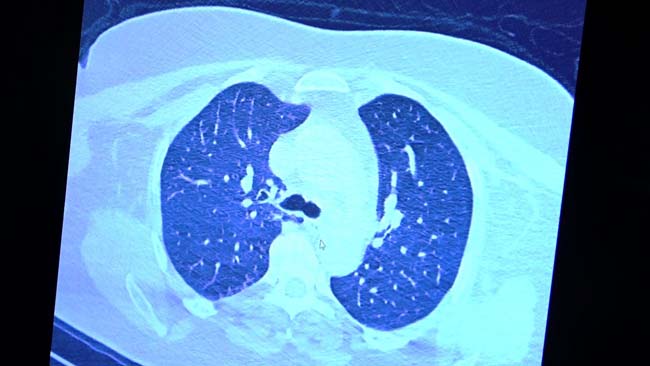

VM Medical Park Samsun Hastanesi’nde görev yapan Göğüs Hastalıkları Kliniği’nden Prof. Dr. Şevket Özkaya da bir hafta ilaç kullanmayan bir pozitif hastanın akciğer tomografisini inceledi. Hasta pozitif haldeyken ilk akciğer tomografisine bakıldı. Tomografide akciğerlerdeki tutulmanın az olduğu gözlemlendi. Akabinde aynı hastanın verilen ilaçları kullanmamış ve 1 hafta boyunca tedaviye uymamış haldeki akciğer tomografisine bakıldı. Sonuç ise ilaç kullanımının önemini ortaya çıkardı. Hastanın akciğer tomografisinde yaygın buzlu camların ve hava yollarının hava yerine ciddi şekilde sıvı ile dolduğu gözlemlendi.

Akciğer tomografisinde oluşan değişim ile ilgili bilgi veren Prof. Dr. Şevket Özkaya, "Ekranda 55 yaşında bir kadın hastamızın filmini görüyorsunuz. Bu kadın hastamız acil servisimize ateş şikâyetiyle geldi ve korona virüsünden şüphe ettik. Testini yaptığımızda ise testin sonucu pozitif geldi. Tomografi çektiğimiz zaman akciğerlerinde henüz ciddi bir tutulum görünmezken hastamız 55 yaşında olduğu için her an ilerleyebilir korkusuyla Sağlık Bakanlığımızın önerdiği ilaçları ve reçeteyi hastanemizden kendisine verdik. Hasta kendini evde karantinaya aldı fakat sonradan öğrendik ki tereddüt ettiği için ilaçlarını kullanmayarak kendini evde tedavisiz bırakmış. Yaklaşık bir hafta sonra aynı hasta acil servisimize bu sefer solunum yetmezliği şikâyetiyle geldi. Solunum yetmezliği gelişince hastanın akciğer tomografisinde ‘buzlu cam’ dediğimiz ve daha ileri konsolide alanların oluştuğunu gördük. Yaygın akciğer harabiyeti dediğimiz bir tablo oluşmuştu. Bu durumda hastada solunum yetmezliği olduğu için yoğun bakıma almak zorunda kaldık" dedi.